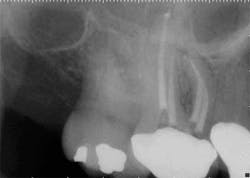

These are my least favorite teeth to treat. Most are heavily restored and the mesial-distal dimension is very small, resulting in no margin for error when locating the pulp chamber. Additionally, there can be significant inclination between the crown and root, and many will have two canals or branching at some level of the canal. (12,15) This lingual inclination of the root results in difficulty obtaining straight-line access into the buccal canal and makes locating the lingual canal almost impossible in some cases, especially if the lingual shelf of dentin is prominent. (Figure 2) Straight-line access into some lingual canals would need to be established through the mid-facial, and this is not a reasonable option for teeth restored with full-coverage crowns. (16)

have two canals. The second canal is lingual

to the main canal, and it is not uncommon for

the two canals to join at the apex. Tooth

No. 24 has a necrotic pulp and based on

the anatomy of teeth Nos. 23 and 26, a

second canal in tooth No. 24 should be expected.